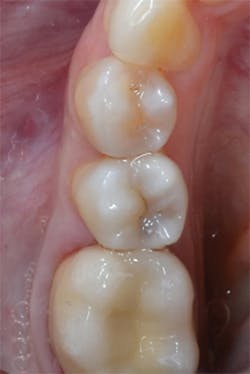

Figure 13: View of teeth Nos. 4 and 5 after curing the final occlusal layer of TPH Spectra composite.

Figure 14: Final restorations on teeth Nos. 4 and 5.